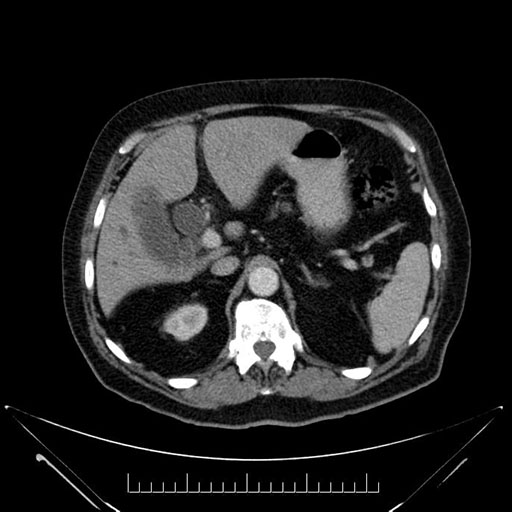

Whipple (pancreaticoduodenectomy) [case 7]

Imaging Analysis

Look through the patient's CT scan to identify any areas of concern for the necessary procedure.

Coronal - stented